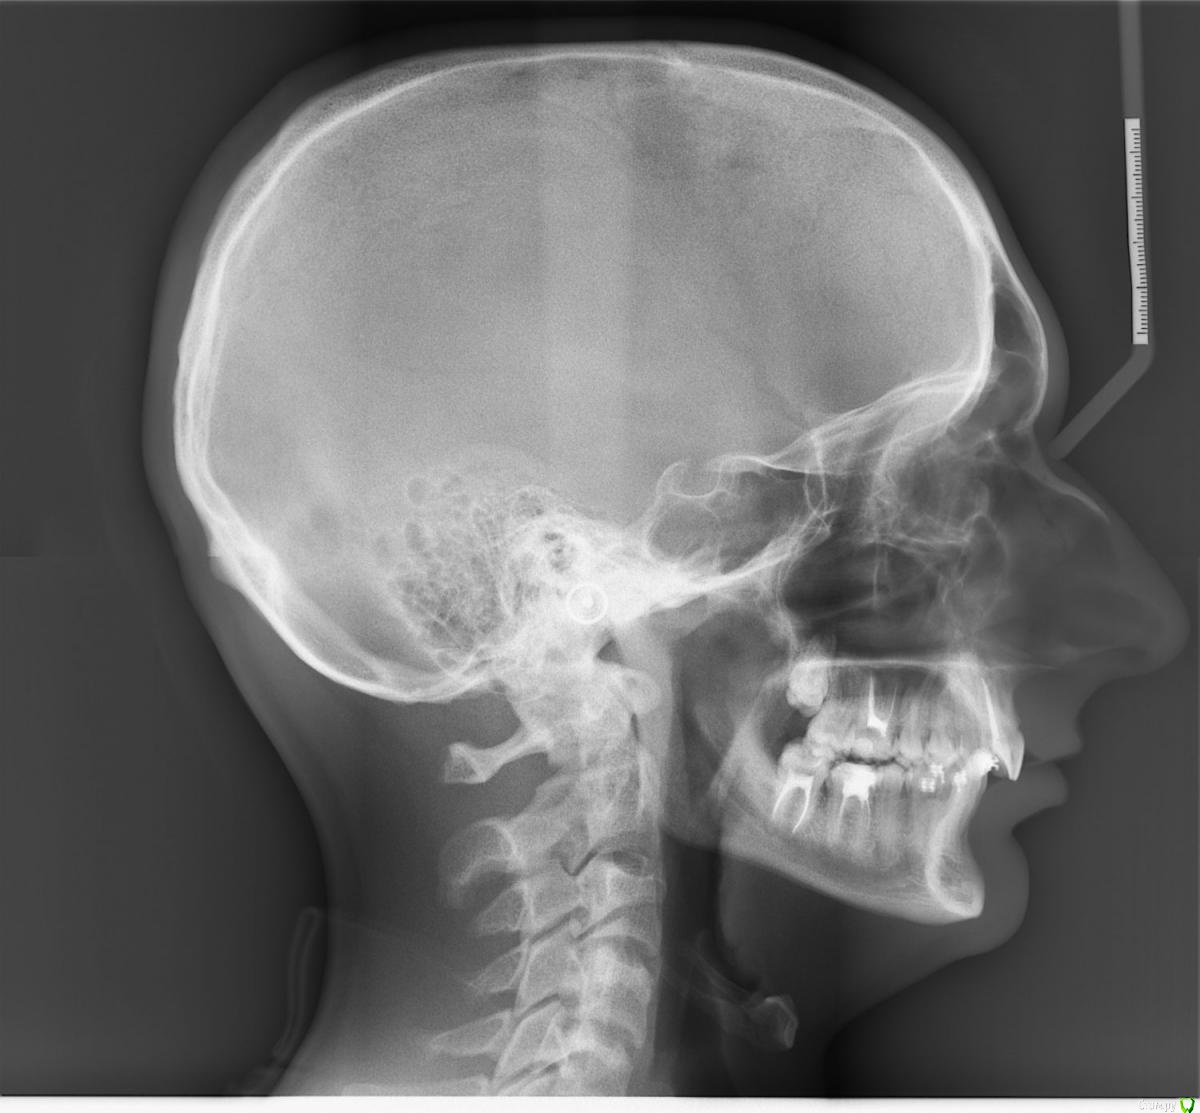

babledy Опубликовано 19 октября, 2015 Поделиться Опубликовано 19 октября, 2015 Доброго времени суток. Зовут меня Ростислав, мне 18 лет, в данный момент учусь и живу в Киеве. То что у меня проблемы с прикусом знал еще с 15 лет, до этого уже один раз проводилось лечение брекетами, но я остался категорически не доволен результатом. На предпоследнем посещении мне сказали что при снятии брекетов будут спиливать около 3-4 миллиметров передних зубов на НЧ и в связи с этим на последнее посещение я не пришел( До сих пор хожу с замочками на НЧ). После такого неудачного лечения я надеялся на профессионализм врачей в столице, но не тут то было. После 4 консультаций в разных клиниках, в первых трех врачи посмотрели меня, не сделав ни одного снимка и диагноз был таков - глубокий дистальный прикус, переразвитие верхней челюсти и недоразвитие нижней(их задача как я понял - просто исправить прикус, не учитывая черты лица). Я категорически не согласен с этим, хоть я и не врач, но как у меня может быть переразвитие ВЧ, если профиль моего лица вогнутый? В последней клинике мне удалось откровенно поговорить с врачом, я рассказал ей что меня не устраивает и она направила меня сделать два снимка. Она сказала нечто иное, что НЧ у меня наоборот нормально развита и так же она мне сказала, что когда мне хотели спиливать нижние передние зубы, то это таким образом мне хотели вылечить кривую Шпея. На консультациях я ожидал, что мне как минимум скажут о недоразвитии ВЧ, скажут что нужно двигать зубы ВЧ вперед, чтобы поправить профиль. Дорогие врачи, к чему я все это завел. Я уже около недели хожу никакой, разочаровался что меня уже вылечить не смогут так, как мне того хотелось или же просто эти "врачи" не хотят усложнять себе жизнь моим нормальным, правильным лечением? Действительно ли у меня переразвитие ВЧ или же нет и какой реальный диагноз моего прикуса, можно ли его лечить? Ссылка на комментарий

m.d.n Опубликовано 19 октября, 2015 Поделиться Опубликовано 19 октября, 2015 Лечить можно, если хотите профиль лицо и тд- то ортогнатическая хирургия вам в помощь. дело не в размере челюстей а в их положении относительо основания черепа Ссылка на комментарий